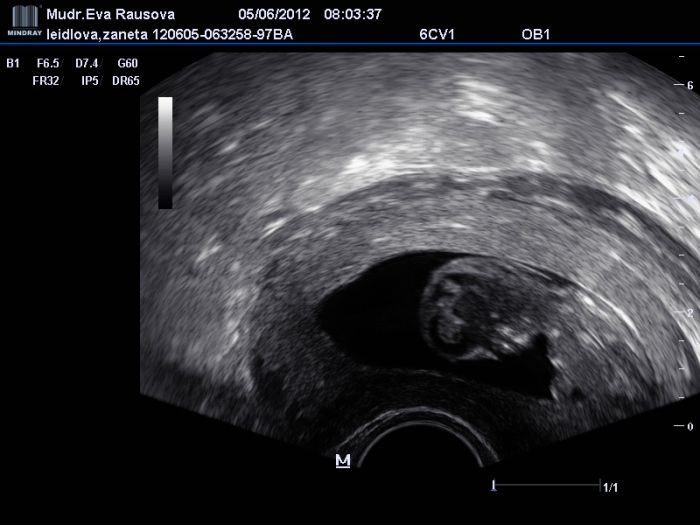

Tak holky, jedna aktuální z 11+0, překvapivě se prcek neuvěřitelně mrskal, dr.se nedařilo udělat ani pořádný obrázek, ale byl to nádherný pocit ho zase po měsíci vidět